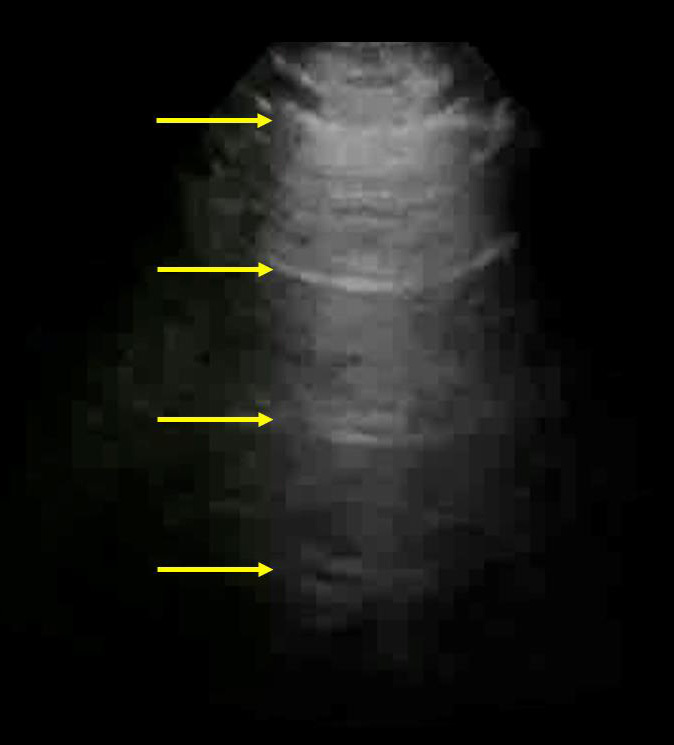

A-Lines - Reverberation Artifacts Graphic

Arrows: Reverberation Artifacts